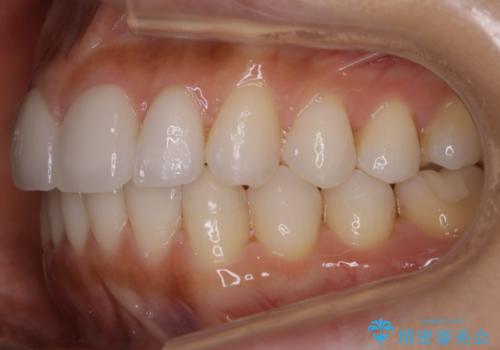

【非抜歯】噛み合わせを整えたい! インビザライン矯正

- 嚙み合わせのズレを主訴にご来院されました。

前歯・奥歯ともにセラミッククラウンで治療されている歯があったため、その歯にあまり影響が出ない範囲内で全体の噛み合わせが良くなるような動きを組み込んで治療を進めることとなりました。